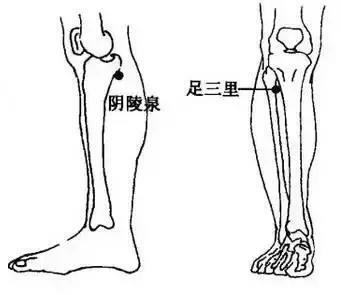

>>>>7. 按揉足三裡、陰陵泉和三陰交

足三裡、陰陵泉和三陰交都是很好的祛濕穴位,濕氣重的人平時可以多揉揉。

① 足三裡穴位於外膝眼下10釐米,用自己的掌心蓋住自己的膝蓋骨,五指朝下,中指盡處便是此穴。

② 屈膝,在脛骨內側髁的下方的凹陷中,就是陰陵泉穴。

在內踝尖上用自己的手指4指之上,按壓有一骨頭,三陰交穴位於脛骨後緣靠近骨邊凹陷處。